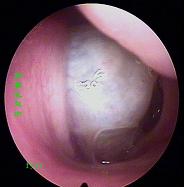

鼻炎长期得不到有效治疗导致鼻息肉以及鼻腔囊肿

经常鼻塞、流脓鼻涕、头痛多为鼻窦炎、鼻息肉等。